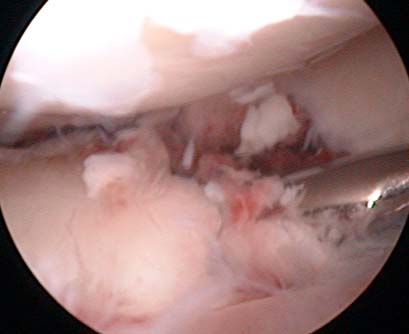

In hospital broken bone labeled Bruchstele Shin fixed with 3 screws Looking into the knee by arthroscope during surgical treatment

After exactly one half-year of untroubled riding pleasure it happens: I have an accident with my idiot-proof senior-citizen-vehicle! Suddenly my daily routine changes drastically: ambulance, university hospital, X-ray (diagnosis: long break in the tibia-plateau, the shin), a cast, knee-puncture, operation (bones fixed back in place with three screws), rehabilitation exercises and laboriously learning to walk again with crutches. A total of 12 days in the hospital and then at first twelve weeks of not being allowed to put more than 10 kg on the leg, otherwise the bones will break again and the whole painful routine will start from the beginning.